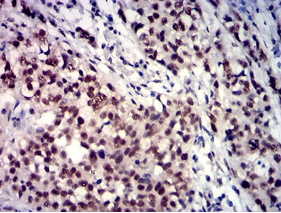

IHC    1/200 - 1/1000